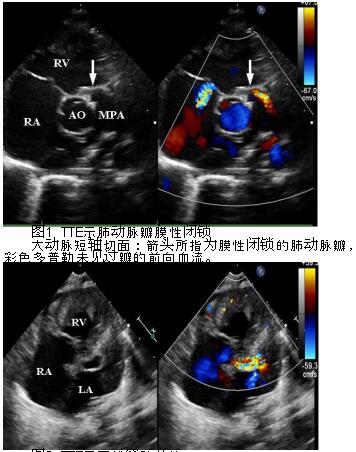

超声心动图在婴幼儿室间隔完整型肺动脉闭锁杂交手术中的临床价值